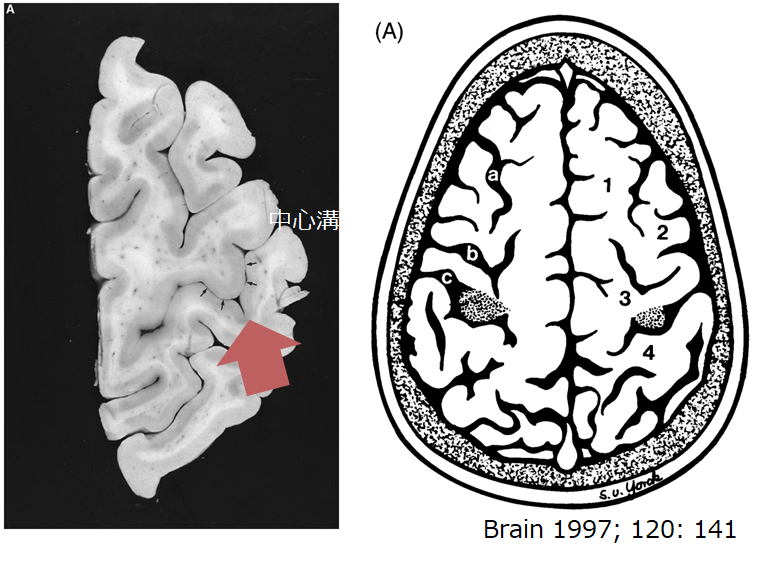

上肢単独麻痺を呈する脳血管障害│医學事始 いがくことはじめ。